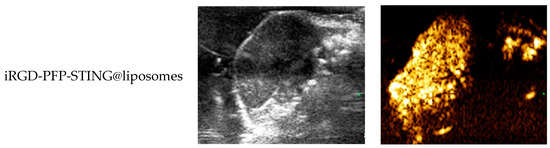

In Vivo Ultrasound Imaging

To evaluate the contrast-enhanced ultrasound effect of the liposomes in vivo, ultrasound imaging experiments were conducted on mice bearing 4T1 breast cancer xenografts. Following the injection of liposomes and subsequent ultrasound irradiation, a significant enhancement of the ultrasound signal was observed in the tumor region in both B-mode and CEUS-mode. Figure 5 illustrates the ultrasound images of the liposomes after destruction. Following 10 min of injection, exposure to LIFU at 3 W/cm2 in pulsed wave mode for three minutes resulted in the formation of hyperechoic regions in the tumor, as observed in both B-mode and CEUS-mode images. This finding indicated that phase transition of the nanoliposomes was successfully induced through ADV. In CEUS-mode, the ultrasound signal intensity in tumors treated with targeted iRGD liposomes was higher compared to non-targeted tumors. These results demonstrated that the developed liposomes enabled real-time monitoring and visualization of the tumor treatment area during drug therapy. In addition, the results confirmed that these liposomes exhibited targeted anti-tumor activity and could be effectively employed for ultrasound imaging, representing a promising therapeutic approach for tumor targeting.

Figure 5.

In vivo ultrasound imaging. The US and CEUS imaging pictures of PFP-STING@liposomes and iRGD-PFP-STING@liposomes obtained at 13 min post-injection. LIFU was applied for 3 min in 4T1 breast cancer xenograft model mice.